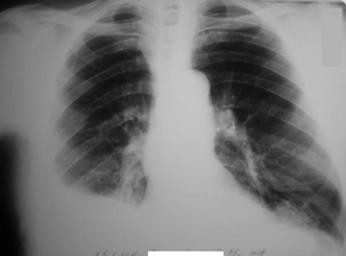

MAKE A MEME View Large Image Гемоторакс, переломы рёбер.jpg ru Зак ытые пе еломы VI VII VIII IX  ёбе сп ава П авосто онний гемото акс Собственная фотог афия Клеткин  ...

Keywords: Гемоторакс, переломы рёбер.jpg ru Зак ытые пе еломы VI VII VIII IX ёбе сп ава П авосто онний гемото акс Собственная фотог афия Клеткин аксим Евгеньевич 2011-01-30 Cc-zero Injuries to the thorax X-rays of the chest